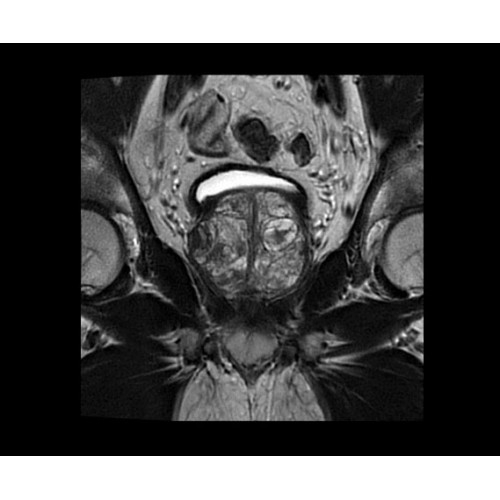

Система SIGNA PET/MR предлагает впечатляющие клинические возможности и открывает доступ к наиболее полным пакетам программных приложений.

• TurboTOF — инновационная технология позволяет корректировать коэффициент затухания сигнала и минимизировать потери анатомических данных, создавая МР-систему для количественной визуализации.

• Q.Clear — в основу технологии легли накопленные знания о том, как минимизировать помехи при реконструкции и получить четкое изображение. При значительном улучшении качества изображения сохраняется точность расчетов. Сочетание технологии TOF и реконструкции Q.Clear — ваш надежный помощник для получения точных и достоверных данных.

• МРТ с функцией нулевого времени эхо (ZTE) отличается точностью, возможностью персональных настроек и отсутствием ионизирующего излучения. Она приходит на смену традиционному исследованию на основе рентгеновского излучения. МРТ с функцией нулевого времени эхо (ZTE) на базе SIGNA ПЭТ/МРТ является более надежной и быстрой по сравнению с системами, использующими сверхмалое время эхо (UTE).

• Приложения для коррекции артефактов движения — используйте наиболее широкий набор инструментов, таких как PROPELLER, PROMO и навигаторы Pencil Beam, позволяющих снизить влияние непроизвольных или физиологических движений на качество изображений.